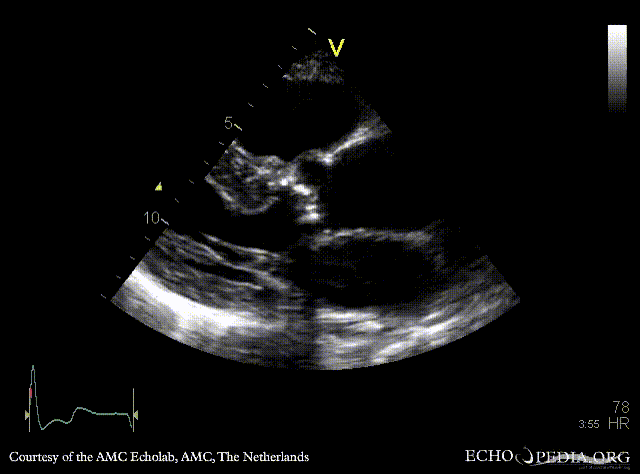

| <html5media height="350" width="279" autoplay="true" loop="true">File:E00772.mp4</html5media> | <html5media height="350" width="279" autoplay="true" loop="true">File:E00773.mp4</html5media> |

| PLAX: concentric hypertrophy of left ventricle, thickend aortic valve | PSAX: concentric hypertrophy of left ventricle |